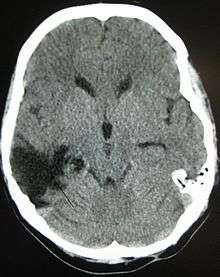

One type of focal injury, cerebral laceration, occurs when the tissue is cut or torn.[30] Such tearing is common in orbitofrontal cortex in particular, because of bony protrusions on the interior skull ridge above the eyes.[24] In a similar injury, cerebral contusion (bruising of brain tissue), blood is mixed among tissue.[15] In contrast, intracranial hemorrhage involves bleeding that is not mixed with tissue.[30]

Hematomas, also focal lesions, are collections of blood in or around the brain that can result from hemorrhage.[3] Intracerebral hemorrhage, with bleeding in the brain tissue itself, is an intra-axial lesion. Extra-axial lesions include epidural hematoma, subdural hematoma, subarachnoid hemorrhage, and intraventricular hemorrhage.[31] Epidural hematoma involves bleeding into the area between the skull and the dura mater, the outermost of the three membranes surrounding the brain.[3] In subdural hematoma, bleeding occurs between the dura and the arachnoid mater.[15] Subarachnoid hemorrhage involves bleeding into the space between the arachnoid membrane and the pia mater.[15] Intraventricular hemorrhage occurs when there is bleeding in the ventricles.[31]